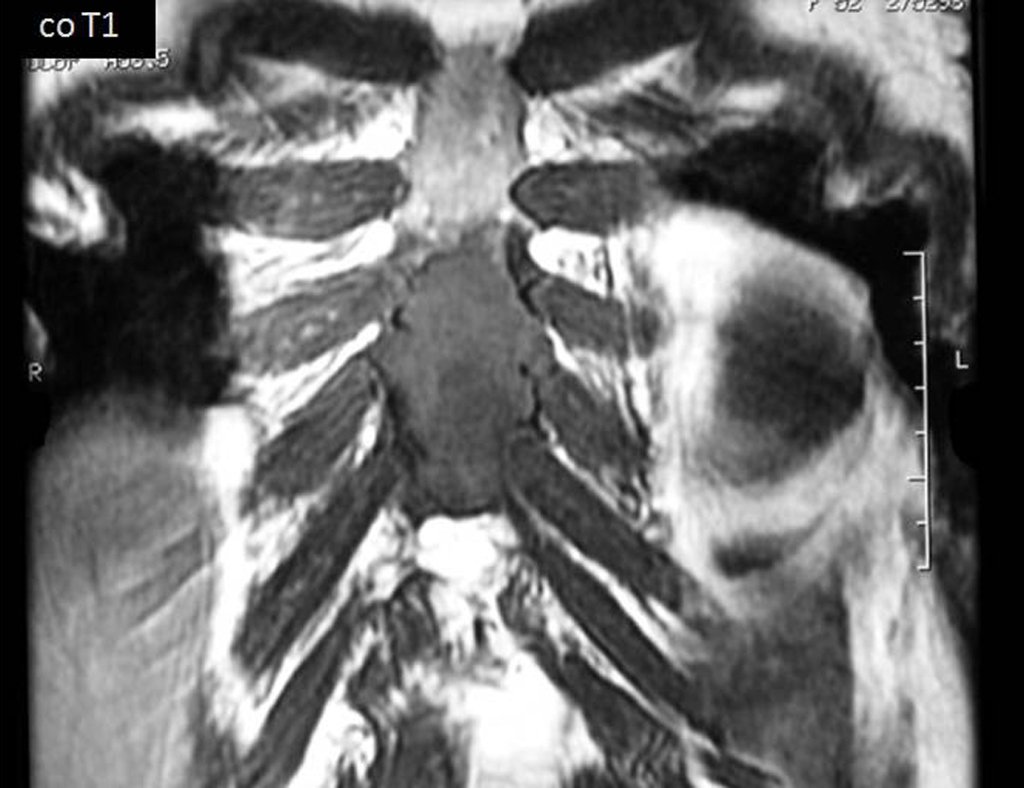

After seven years and eight months of treatment for the thigh tumor and four years and two months of resection of the sten, the patient presented metastasis in the right calf (Figures 36 and 37) and the staging revealed a lesion in the thoracic vertebra, T11 and in the retroperitoneum (Figures 38 and 39).